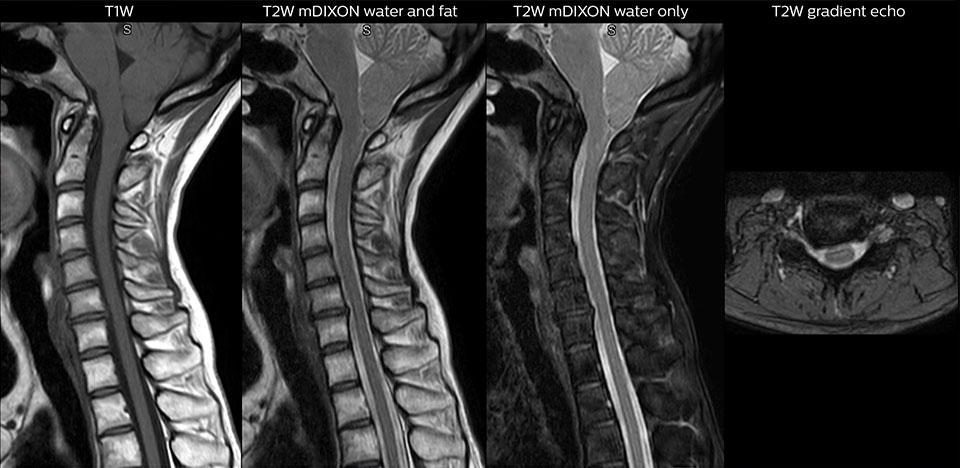

“For the thoracic and cervical spine routine non-contrast exam, for example, we perform one mDIXON T2 TSE sequence, which provides us with two outputs: the fat-and-water-together T2-weighted images, as well as the water-only sagittal T2-weighted images. And then we also perform an axial gradient echo exam.”

cervical spine mri in ed

Cervical spine routine exam

This patient presented with headache that was worse with neck flexion and we see a Chiari 1 malformation with low-lying cerebellar tonsils as well as some degenerative cervical thrombolytic change.